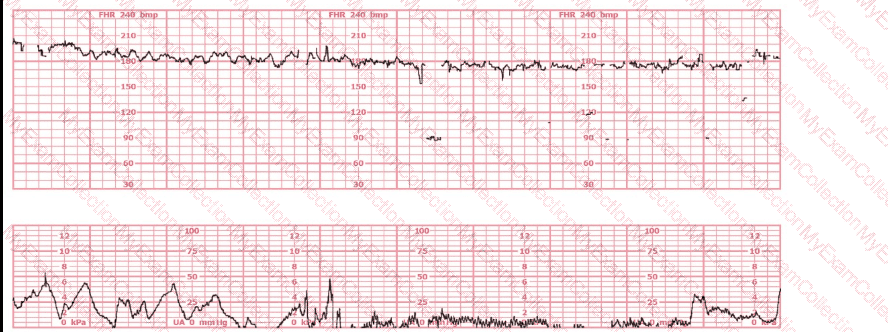

A woman in labor has been pushing for 4 hours. For the last 2 hours, there have been recurrent variable decelerations. Variability has evolved from moderate to minimal. Cervical exam is 10/100%/+2, fetal head OP. There has been no fetal descent for the last 45 minutes. Based on the tracing shown, the most reasonable approach is